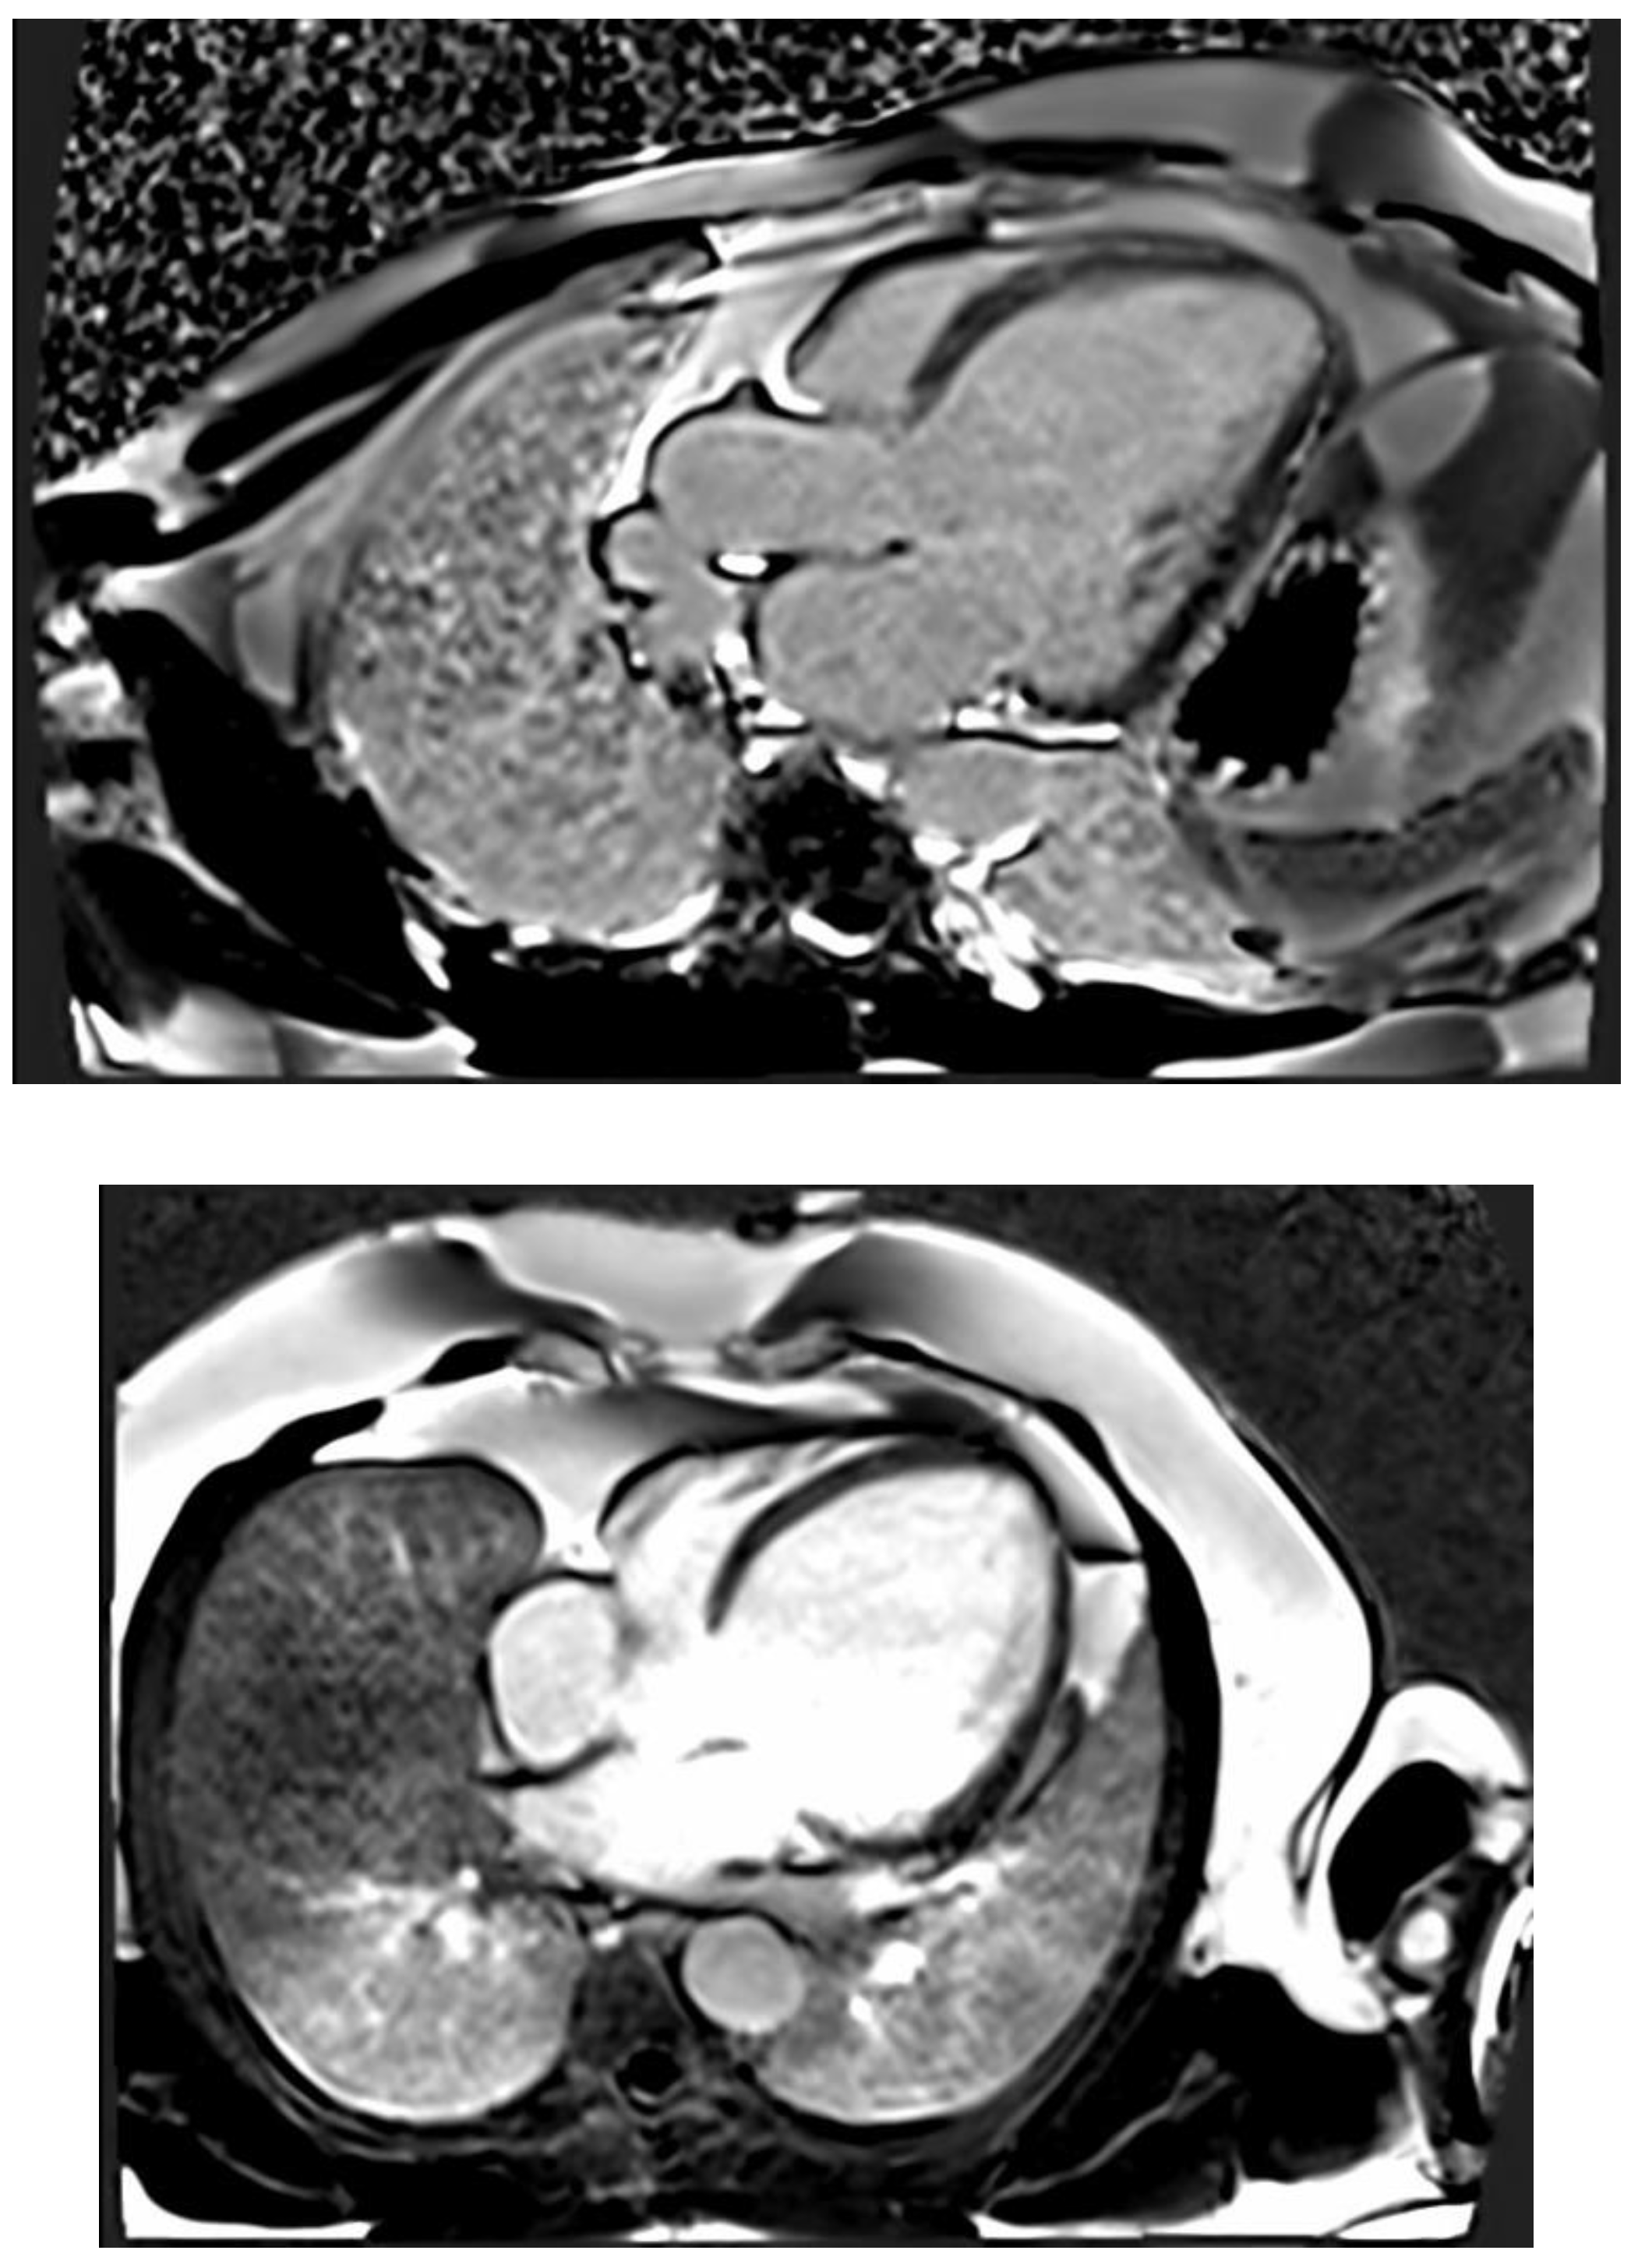

CMR imaging has become the most reliable method for evaluating the size and function of the ventricles. It should be performed in all patients who have recently been diagnosed with cardiomyopathy. CMR can offer comprehensive anatomical and physiological data that surpasses that of TTE. Additionally, CMR can provide insights into cardiac tissue features, including inflammation and fibrosis, through the use of late gadolinium enhancement (LGE). CMR has the benefits of being non-invasive and not requiring an acoustic window, while also allowing for the analysis of tissue characteristics. The latter benefit is especially crucial in diagnosing non-compaction LV cardiomyopathy (Figure 4) , ARVC, myocarditis, amyloidosis, sarcoidosis, and other types of inflammatory diseases, as well as haemochromatosis. Standard initial examination should regularly include cine imaging sequences, T2-weighted sequences, pre- and post-contrast T1 mapping, and LGE. These findings should be evaluated alongside genetic results and other clinical features by experienced professionals in cardiac imaging and heart muscle disease assessment.

Regular follow-up CMR should be conducted every 2-5 years, depending on the initial severity and clinical course of the disease. This can help assess the progression of the disease and the effectiveness of therapy [4]. The existence of LGE is linked to the possibility for arrhythmias and more severe illness. Diseases connected to DSP and FLNC frequently exhibit a fibrosis pattern resembling a ring around the outer layer of the heart, known as subepicardial fibrosis. This observation may suggest the need for considering the installation of an implantable cardioverter-defibrillator (ICD). CMR has the capability to identify illness in persons who do not show any symptoms and may also be used to track the progression of the disease [68].

The existence of LGE is linked to the possibility for arrhythmias and more severe illness. Diseases connected to DSP and FLNC frequently exhibit a fibrosis pattern resembling a ring around the outer layer of the heart, known as subepicardial fibrosis, as presented in Figure 5. This observation may suggest the need for considering the installation of an implantable cardioverter-defibrillator (ICD). CMR has the capability to identify illness in persons who do not show any symptoms and may also be used to track the progression of the disease [68].